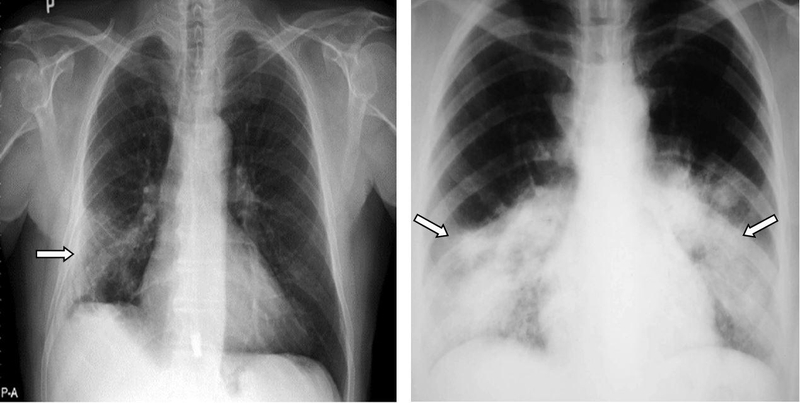

Hình ảnh X quang phổi bình thường ở người mắc bệnh COPD giai đoạn sớm, hình ảnh phế nang không giãn. Kết quả X quang thường cho thấy hình ảnh khí phế thũng khi ở giai đoạn muộn và có hội chứng phế quản.

X quang phổi giúp loại trừ một số bệnh phổi khác như: U phổi, lao phổi, giãn phế quản, xơ phổi... Ngoài ra chụp X quang phổi có thể phát hiện các bệnh đồng mắc với COPD như: Tràn khí màng phổi, suy tim, tràn dịch màn phổi, các bất thường khung xương lồng ngực, cột sống…